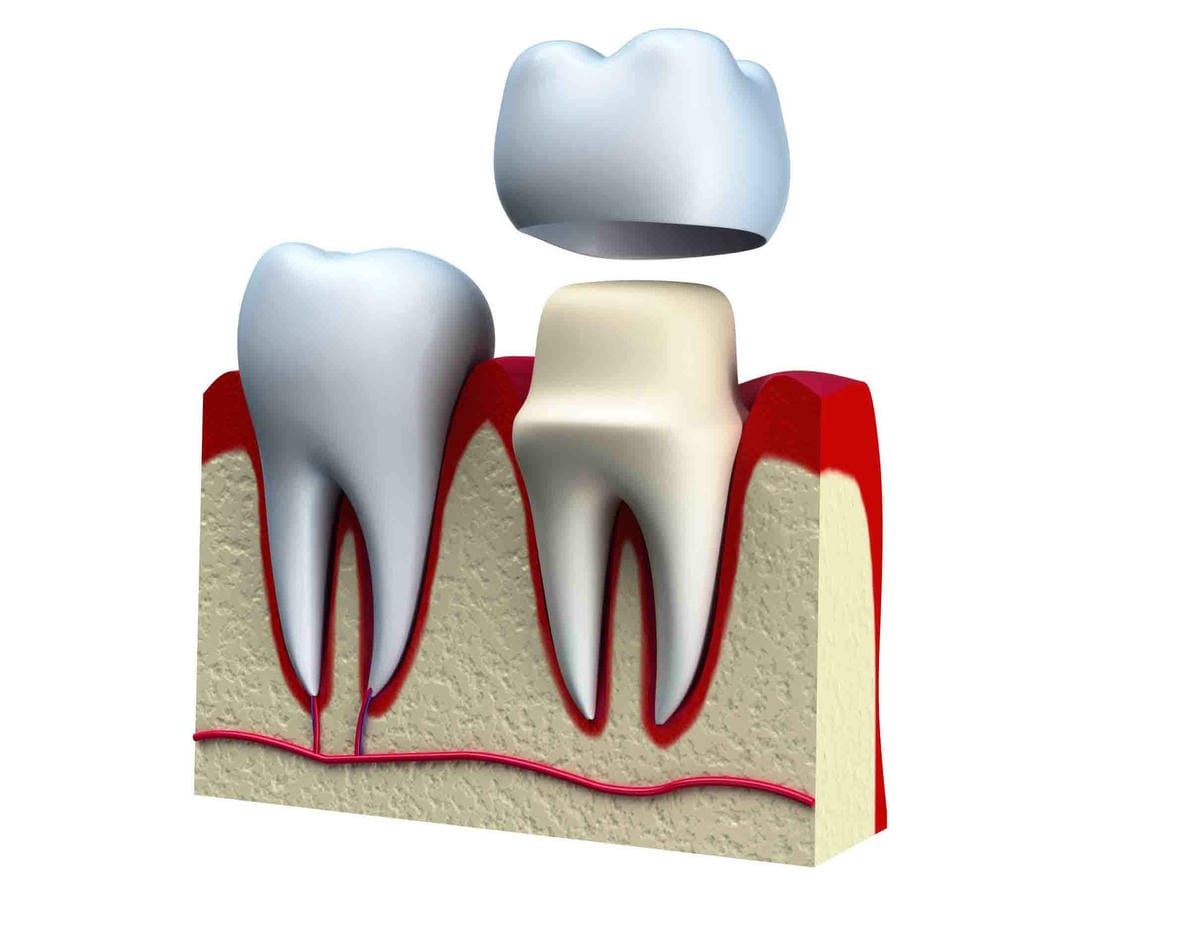

殊不知… 如果牙根情況良好其實可以只做單一顆牙冠假牙即可

所以李醫師解說下,Sunny才了解自己要做的是這樣(如下)